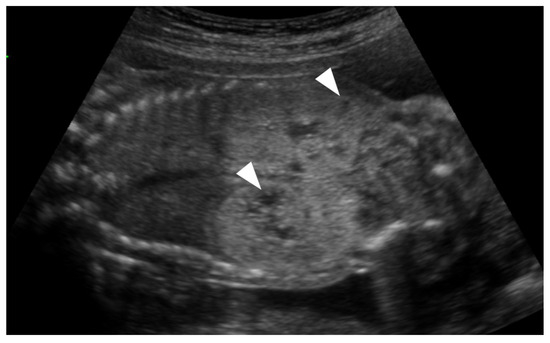

Case Report: Atypical Nodular Dermatofibrosis and Renal Cysts in a Bichon Frise with a BRCA2 Mutation and No FLCN Mutation

A 10-year-old intact female Bichon Frise presented with multiple firm skin nodules on all four limbs. The nodules progressively increased in number and size over seven months. Diagnostic tests included cytology of fine-needle aspirates, histopathology of skin biopsies, radiography, and abdominal ultrasonography. Cytology [...] Read more.

A 10-year-old intact female Bichon Frise presented with multiple firm skin nodules on all four limbs. The nodules progressively increased in number and size over seven months. Diagnostic tests included cytology of fine-needle aspirates, histopathology of skin biopsies, radiography, and abdominal ultrasonography. Cytology revealed spindle-shaped mesenchymal cells and extracellular matrix components, and histopathology confirmed ND characterized by mature collagen deposition without evidence of malignancy. Ultrasonography detected multiple kidney cysts bilaterally, although their exact nature (benign or malignant) could not be confirmed histologically. Genetic analysis was performed, revealing no mutation in the traditionally implicated FLCN gene but multiple nonsynonymous mutations in the BRCA2 gene. This case suggests a potential association between BRCA2 gene mutations and the development of ND with renal cystic lesions, broadening the known genetic causes beyond the commonly reported FLCN mutation. Regular genetic screening and close monitoring of dermatological and renal conditions in atypical breeds are recommended. To the best of current knowledge, this is the first case report demonstrating ND and renal cysts associated with BRCA2 mutations in a Bichon Frise. Full article